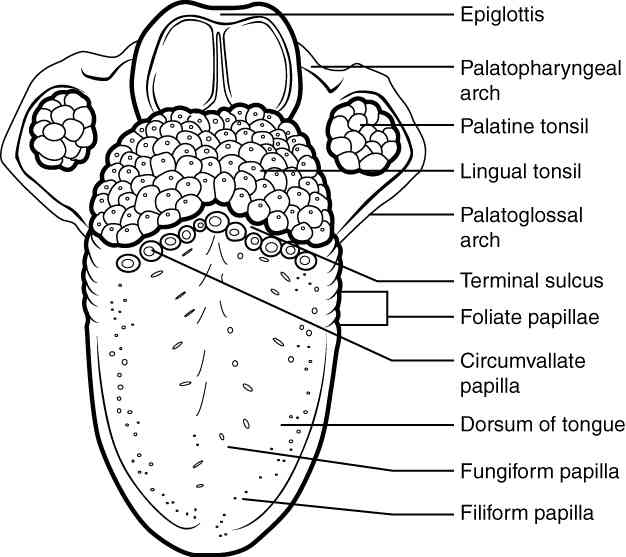

This page is under construction. For now, it is just a resource of the images found in the OpenStax Anatomy and Physiology Handbook. It wil slowly change into a revision tool. Each slide has a number. Use this to refer to the slide. When completed, it will have an unlabelled section, with labelled slides in parallel. On the unlabelled slides, write your answer and use the labelled slide to assess yourself. Keep track by also noting the number on each slide. Improvement at each attempt is important, more so than full marks on a first attempt.